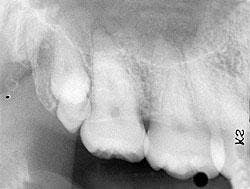

A 25-year-old female visited a dental office for a routine checkup. Radiographic examination revealed two tooth-like radiopacities in the right maxillary tuberosity area.

Based on the clinical examination of the patient, selected periapical radiographs and bitewing films were ordered. A review of the periapical films revealed two tooth-like radiopacities in the right maxillary tuberosity area (see radiograph). The location of the radiopacities was distal to the erupted third molar. No other abnormalities were noted on the radiographs.

Dental radiographs (periapical, bitewing, and panoramic films) can be used to identify unerupted supernumerary teeth. Such teeth can be identified on a radiograph after the ages three or four (primary dentition) and after the ages nine to 12 (permanent dentition). Although the shape and size of supernumerary teeth may vary, the radiographic appearance of the tooth (radiopaque enamel and dentin) is identical to the other teeth on the film.